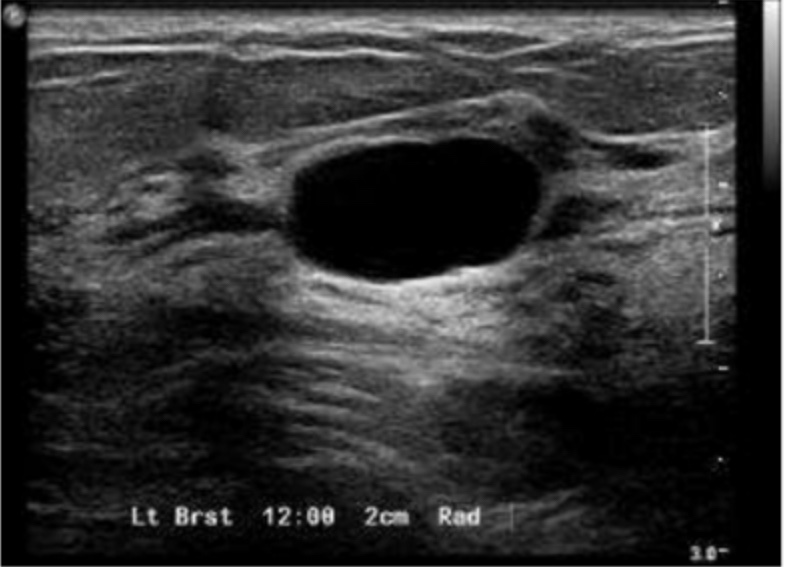

Simple Breast Cyst

• Simple cysts on ultrasound are:

• Anechoic, well circumscribed, with smooth walls and posterior enhancement, as depicted in the image